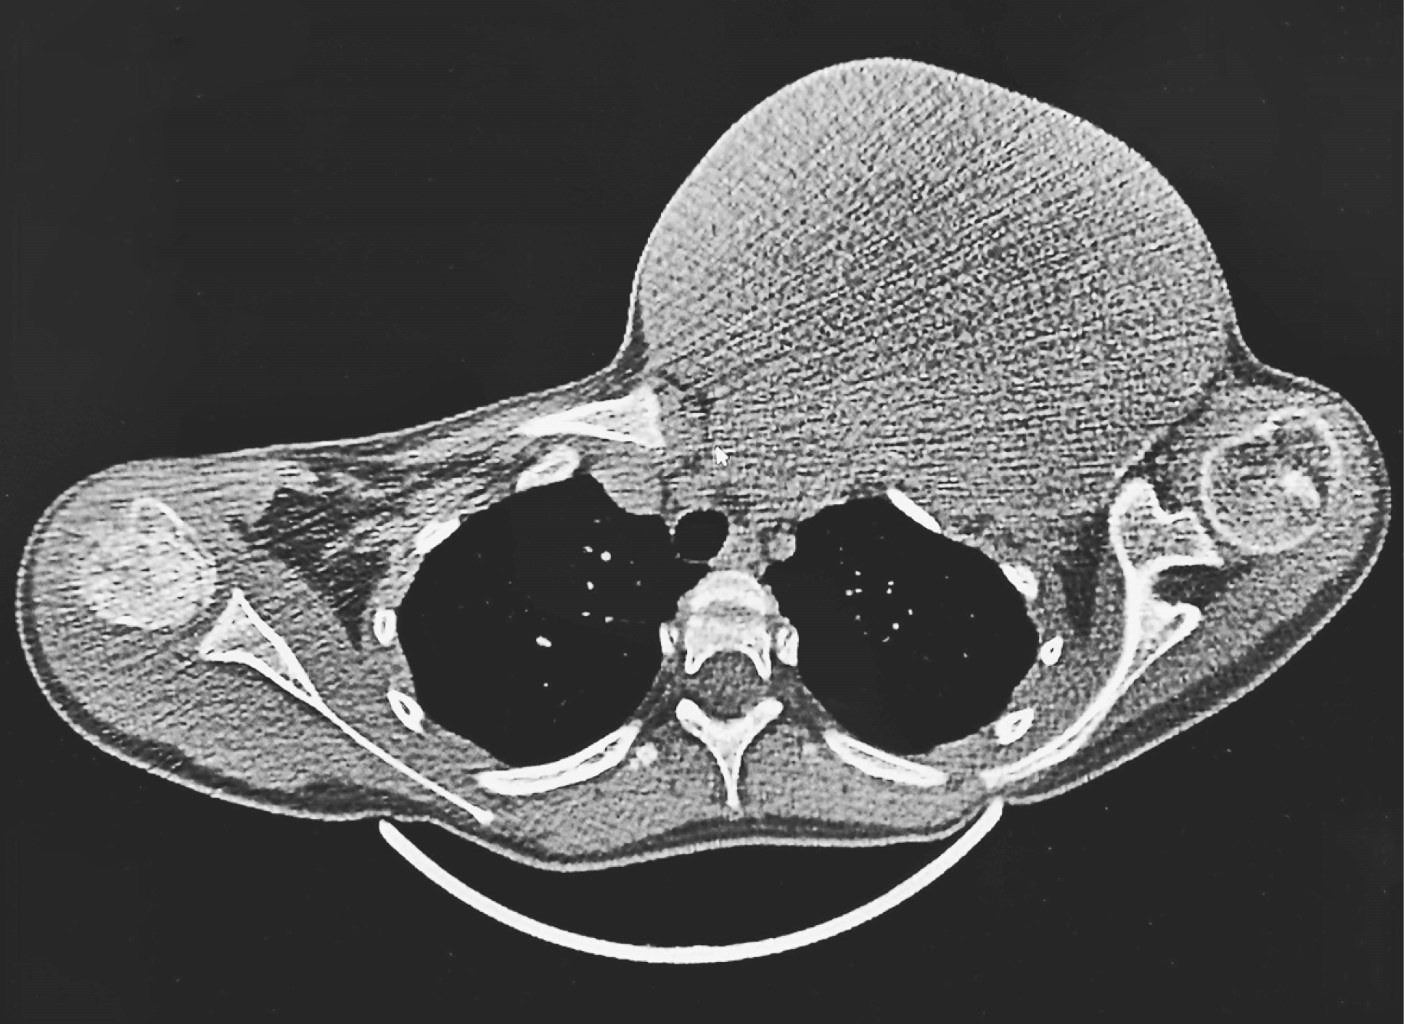

By conventional radiology, the absence of the clavicle was observed with its replacement by a soft tissue mass with neoplastic characteristics. Computer tomography (Figures 1 and 2) and magnetic resonance imaging (Figure 3) show a neoplastic lesion which replaces the left clavicle and generates compression and vascular displacement. No evidence of sternal and/or acromial involvement is seen. The lesion rests on the first and second left ribs, however tumor involvement of it is not proven due to continuity. Both studies showed tracheal and thyroid shift to the right and the neurovascular structures of the neck (internal and external jugular veins, subclavian vein, common carotid artery and brachial plexus) are shown compressed and displaced. By magnetic resonance imaging, T1-weighted sequences showed isointensity to muscle, and T2-weighted sequences showed heterogeneous hyperintensity (Figure 3).

Figure 1

Figure 2